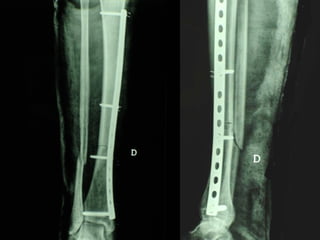

Dal Gennaio 2000 al Febbraio 2006 abbiamo trattato 167 fratture chiuse  con placca percutanea  in 164 pazienti :  27 lesioni diafisarie di gamba, 12 piloni tibiali ,  11 fratture prossimali di tibia, 36 fratture sovracondiloidee di femore, 17 fratture diafisarie di femore, 43 fratture metaepifisarie prossimali di omero, 21 diafisarie d’omero.  156 guarigioni 8 fallimenti

I buoni risultati ottenuti dipendono da 5 punti fondamentali:   una accurata riduzione percutanea della frattura  precise vie di accesso  l’utilizzo della placca che consenta il più lungo braccio di leva possibile il pretensionamento della placca  una sintesi con un ridotto numero di viti

Placche lunghe e pretensionate

Placche lunghe e pretensionate Sintesi con un ridotto numero di viti

VANTAGGI CHIRURGIA MININVASIVA Mini Open Inserimento della placca sottocutaneo per scivolamento Viti percutanee Preservazione dei tessuti molli Ridotto danno vascolare Rapida ripresa funzionale